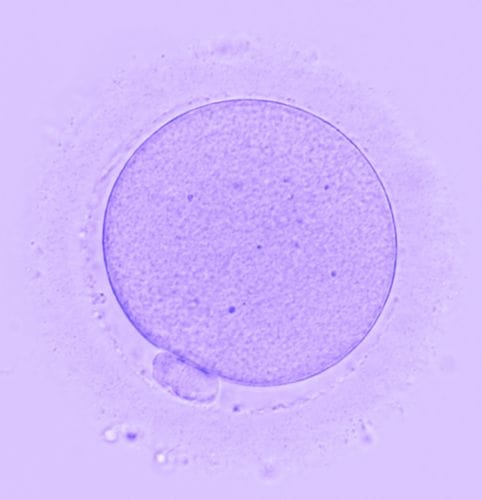

In this webinar, featuring talks by our Chief Medical Officer, Dr. Dan Nayot and our Head of Clinical Embryology & Scientific Operations, Jullin Fjeldstad, we explore the science behind our AI-powered oocyte assessment tools—and how they’re being used in clinics to support lab decision-making, patient counselling, and treatment planning.